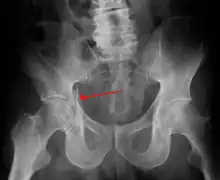

| Acetabular fracture as seen on plain X-ray |

Fractures of the acetabulum occur when the head of the femur is driven into the pelvis. This injury is caused by a blow to either the side or front of the knee and often occurs as a dashboard injury accompanied by a fracture of the femur.[1]